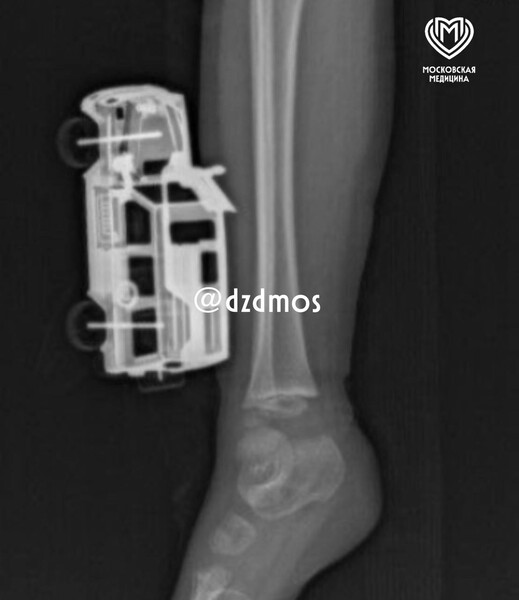

Столичные врачи спасли четырехлетнего мальчика с игрушечной машинкой в ноге

В Москве врачи спасли мальчика с игрушечной машинкой в ноге

В Москве четырехлетний мальчик упал на игрушечную машинку и оказался в больнице. Об этом сообщает Telegram-канал «Московская медицина».

По словам родителей, ребенок прыгнул с кровати у себя дома и неудачно упал на игрушку правой голенью. Машинка повредила мягкие ткани, ее части вошли глубоко и достигли подкожножировой клетчатки.

Пострадавшего мальчика доставили в больницу, где ему сделали рентген, чтобы исключить повреждение костей. После этого медики удалили игрушку и провели хирургическую обработку образовавшейся на ноге ребенка раны. Через сутки малолетнего пациента уже выписали домой.